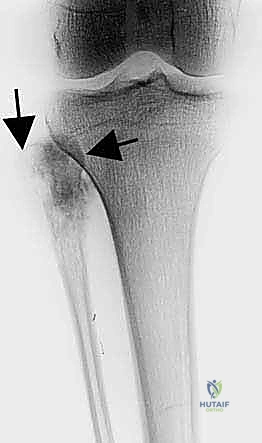

- الأشعة السينية (X-rays): الخطوة الأولى. تظهر التغيرات في الهيكل العظمي، تآكل العظم، أو التفاعلات السمحاقية (Periosteal reaction) التي تدل على وجود ورم.

* الساركوما العظمية (Osteosarcoma): الورم الخبيث الأكثر شيوعاً في العظام، وغالباً ما يصيب الأطفال والشباب. يتميز بنمو سريع وتدمير للعظم.

* ساركوما إيوينغ (Ewing Sarcoma): يصيب عادة الأطفال والمراهقين، وينشأ في تجويف النخاع العظمي للشظية.

* أورام الخلايا العملاقة (Giant Cell Tumors): شائعة في نهايات العظام الطويلة وتميل للعودة إذا لم يتم استئصالها بالكامل.